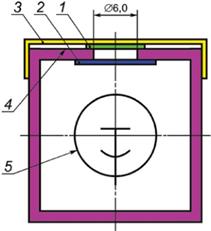

Должен использоваться ДЕТЕКТОР ИЗЛУЧЕНИЯ, который состоит из ЛЮМИНЕСЦЕНТНОГО ЭКРАНА и фотодетектора (см. рисунок 2). ЛЮМИНЕСЦЕНТНЫЙ ЭКРАН изготовляют из сцинтиллятора из активированного тербием оксисульфида гадолиния (GOS, Gd2O2S:Tb), предпочтительно без красителя.

1 - ЛЮМИНЕСЦЕНТНЫЙ ЭКРАН; 2 - свинцовое стекло; 3 - крышка; 4 - выходная плоскость ЛЮМИНЕСЦЕНТНОГО ЭКРАНА; 5 - фотодетектор

Рисунок 2 - ДЕТЕКТОР ИЗЛУЧЕНИЯ

Нагрузка сцинтиллятора должна быть

a) для ОТСЕИВАЮЩИХ РАСТРОВ общего применения - (75 ± 10) мг·см-2;

b) для МАММОГРАФИЧЕСКИХ ОТСЕИВАЮЩИХ РАСТРОВ - (30 ± 3) мг·см-2.

Примечание - Указанный во втором издании сцинтилляционный материал, вольфрамат кальция, больше не доступен на рынке. Современное решение - это GOS, который нетоксичен и негигроскопичен в отличие от йодида цезия, легированного таллием (CsI:TI). Результаты экспериментов показывают эквивалентный результат для сцинтилляторов из вольфрамата кальция и GOS.

Диаметр измеряемого поля - (6,0 ± 0,5) мм.

Яркость ЛЮМИНЕСЦЕНТНОГО ЭКРАНА измеряют, используя фотодетектор, который должен быть чувствительным в диапазоне энергий создаваемых фотонов.